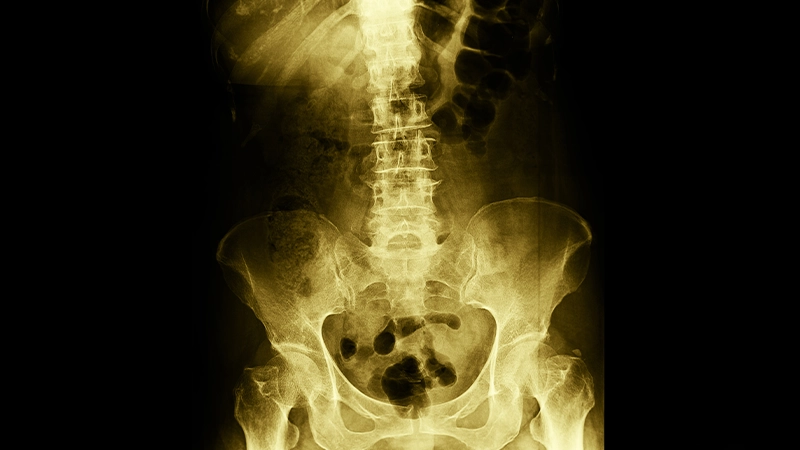

Doktorlar, kalça kireçlenmesini değerlendirirken hastanın anamnezini alır, fizik muayene gerçekleştirir ve ağrının derecesini ve eklem hareketliliğini incelerler. Kesin tanı koymak için genellikle röntgen, MRI veya CT gibi görüntüleme yöntemleri kullanılmaktadır. Bu görüntüleme teknikleri, eklemdeki kireçlenme derecesini, kıkırdak hasarını ve eklemde oluşan osteofitleri ortaya çıkarır.